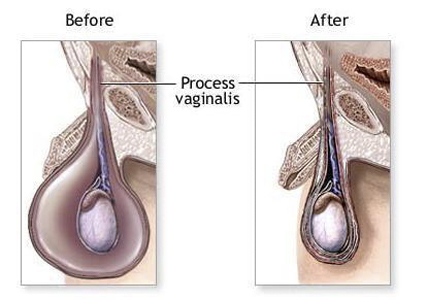

A:精索鞘膜積液多半為先天形成,要了解其形成的原因先要了解部分解剖。睪丸在胎兒時期位於腹腔內,在出生前後部分腹膜,隨著睪丸沿著腹股溝管下降,直降到陰囊當中,形成睪丸的固有鞘膜,沿途鞘膜逐漸就會閉鎖形成纖維索條。如果出生以後部分閉鎖不全,就會在各……